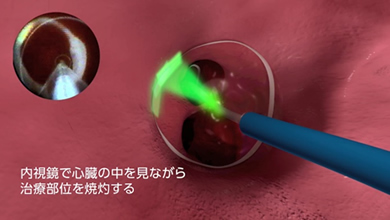

レーザーバルーン

レーザーバルーンは、肺静脈入口部に膨らませたバルーンを留置、バルーン内部に搭載された内視鏡で心臓の中を観察しながらレーザーエネルギーの照射により焼灼を行う最新のアブレーション治療になります。

内視鏡を用いて目視しながら治療することにより、従来の高周波アブレーションと比較してより均一で連続的な焼灼線の作成が可能であること、バルーンのサイズ調整が可能であり様々な形態の肺静脈に対応可能な事が利点です。

また、部位ごとにエネルギー出力を調節できることから、治療効果を高めつつ、肺静脈狭窄や食道障害などの合併症リスクを抑えられることができます。

発作性心房細動をレーザーバルーンで治療した場合の長期非再発率は80%以上であったと報告されています。(※長期非再発率はJCS2021での発表)